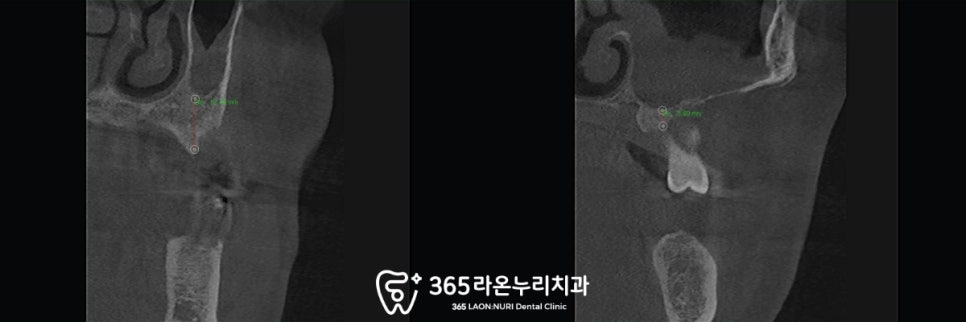

다만 그전에 ct를 찍어

정확한 치조골의 두께와 상태를

먼저 파악해 보았는데요,

부위에 따라 다르긴 하나

전반적으로 골소실이 매우 심하고

뼈도 많이 녹아있습니다.

또한 픽스처를 심기에는

어느 정도 깊이가 확보돼야

안전하게 심을 수 있는데,

이 케이스에서는

그 거리도 아슬아슬한 곳이 많습니다.